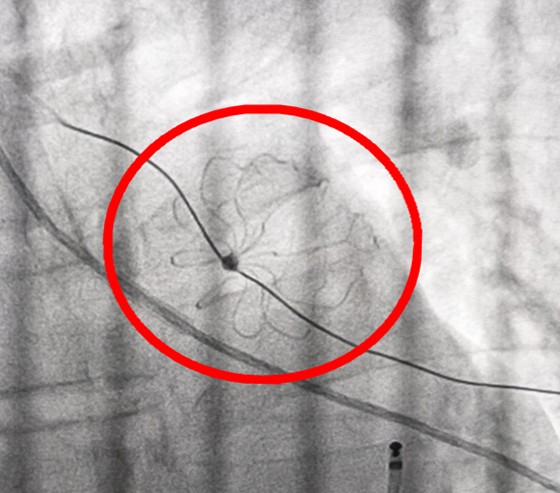

术后成功封堵左心耳开口

4月11日,在介入导管室、心胸外科、放射科等多学科联合协作下,手术如期进行。术中,造影显示患者左心耳远端分布发达的梳状肌呈菜花状,极易造成血流瘀滞,继而形成血栓引发脑卒中等栓塞的危险。彭道地副教授团队首先为患者成功实施射频消融术,遂即将一枚直径3.3厘米的“左心耳封堵伞”植入左心耳,成功封堵左心耳开口,手术过程顺利。术后,周先生恢复窦性心律,继续规范药物治疗,目前恢复良好。